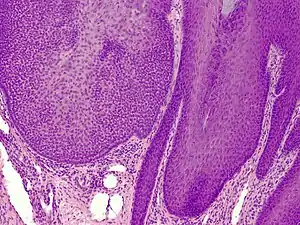

Trichilemmoma (also known as "tricholemmoma"[1]) is a benign cutaneous neoplasm that shows differentiation toward cells of the outer root sheath.[2]: 673 [3] The lesion is often seen in the face and neck region. Multifocal occurrence is associated with Cowden syndrome, in which hamartomatous intestinal polyposis is seen in conjunction with multiple tricholemmoma lesions.

A trichilemmoma on a forehead